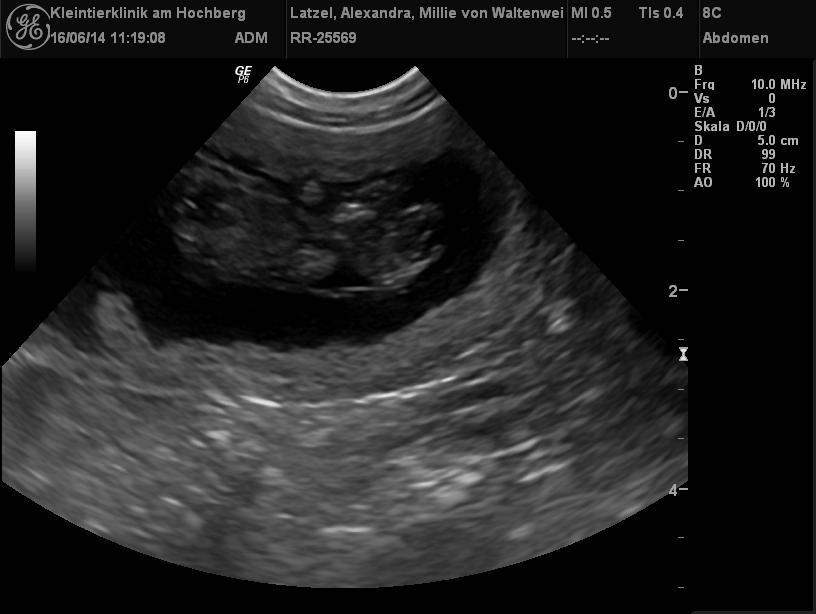

| 25.06.2014 |

| Hurra, Millie ist schwanger! |

| Millie war zum Decken bei Vincent vow for verity von der kleinen Arche!

Sie sind ein wirklich schönes Paar! Nun freuen wir uns sehr auf die Welpis aus dieser Verbindung, die wir Mitte Juli erwarten! |

| Hier die Ultraschallbilder zum Beweis |